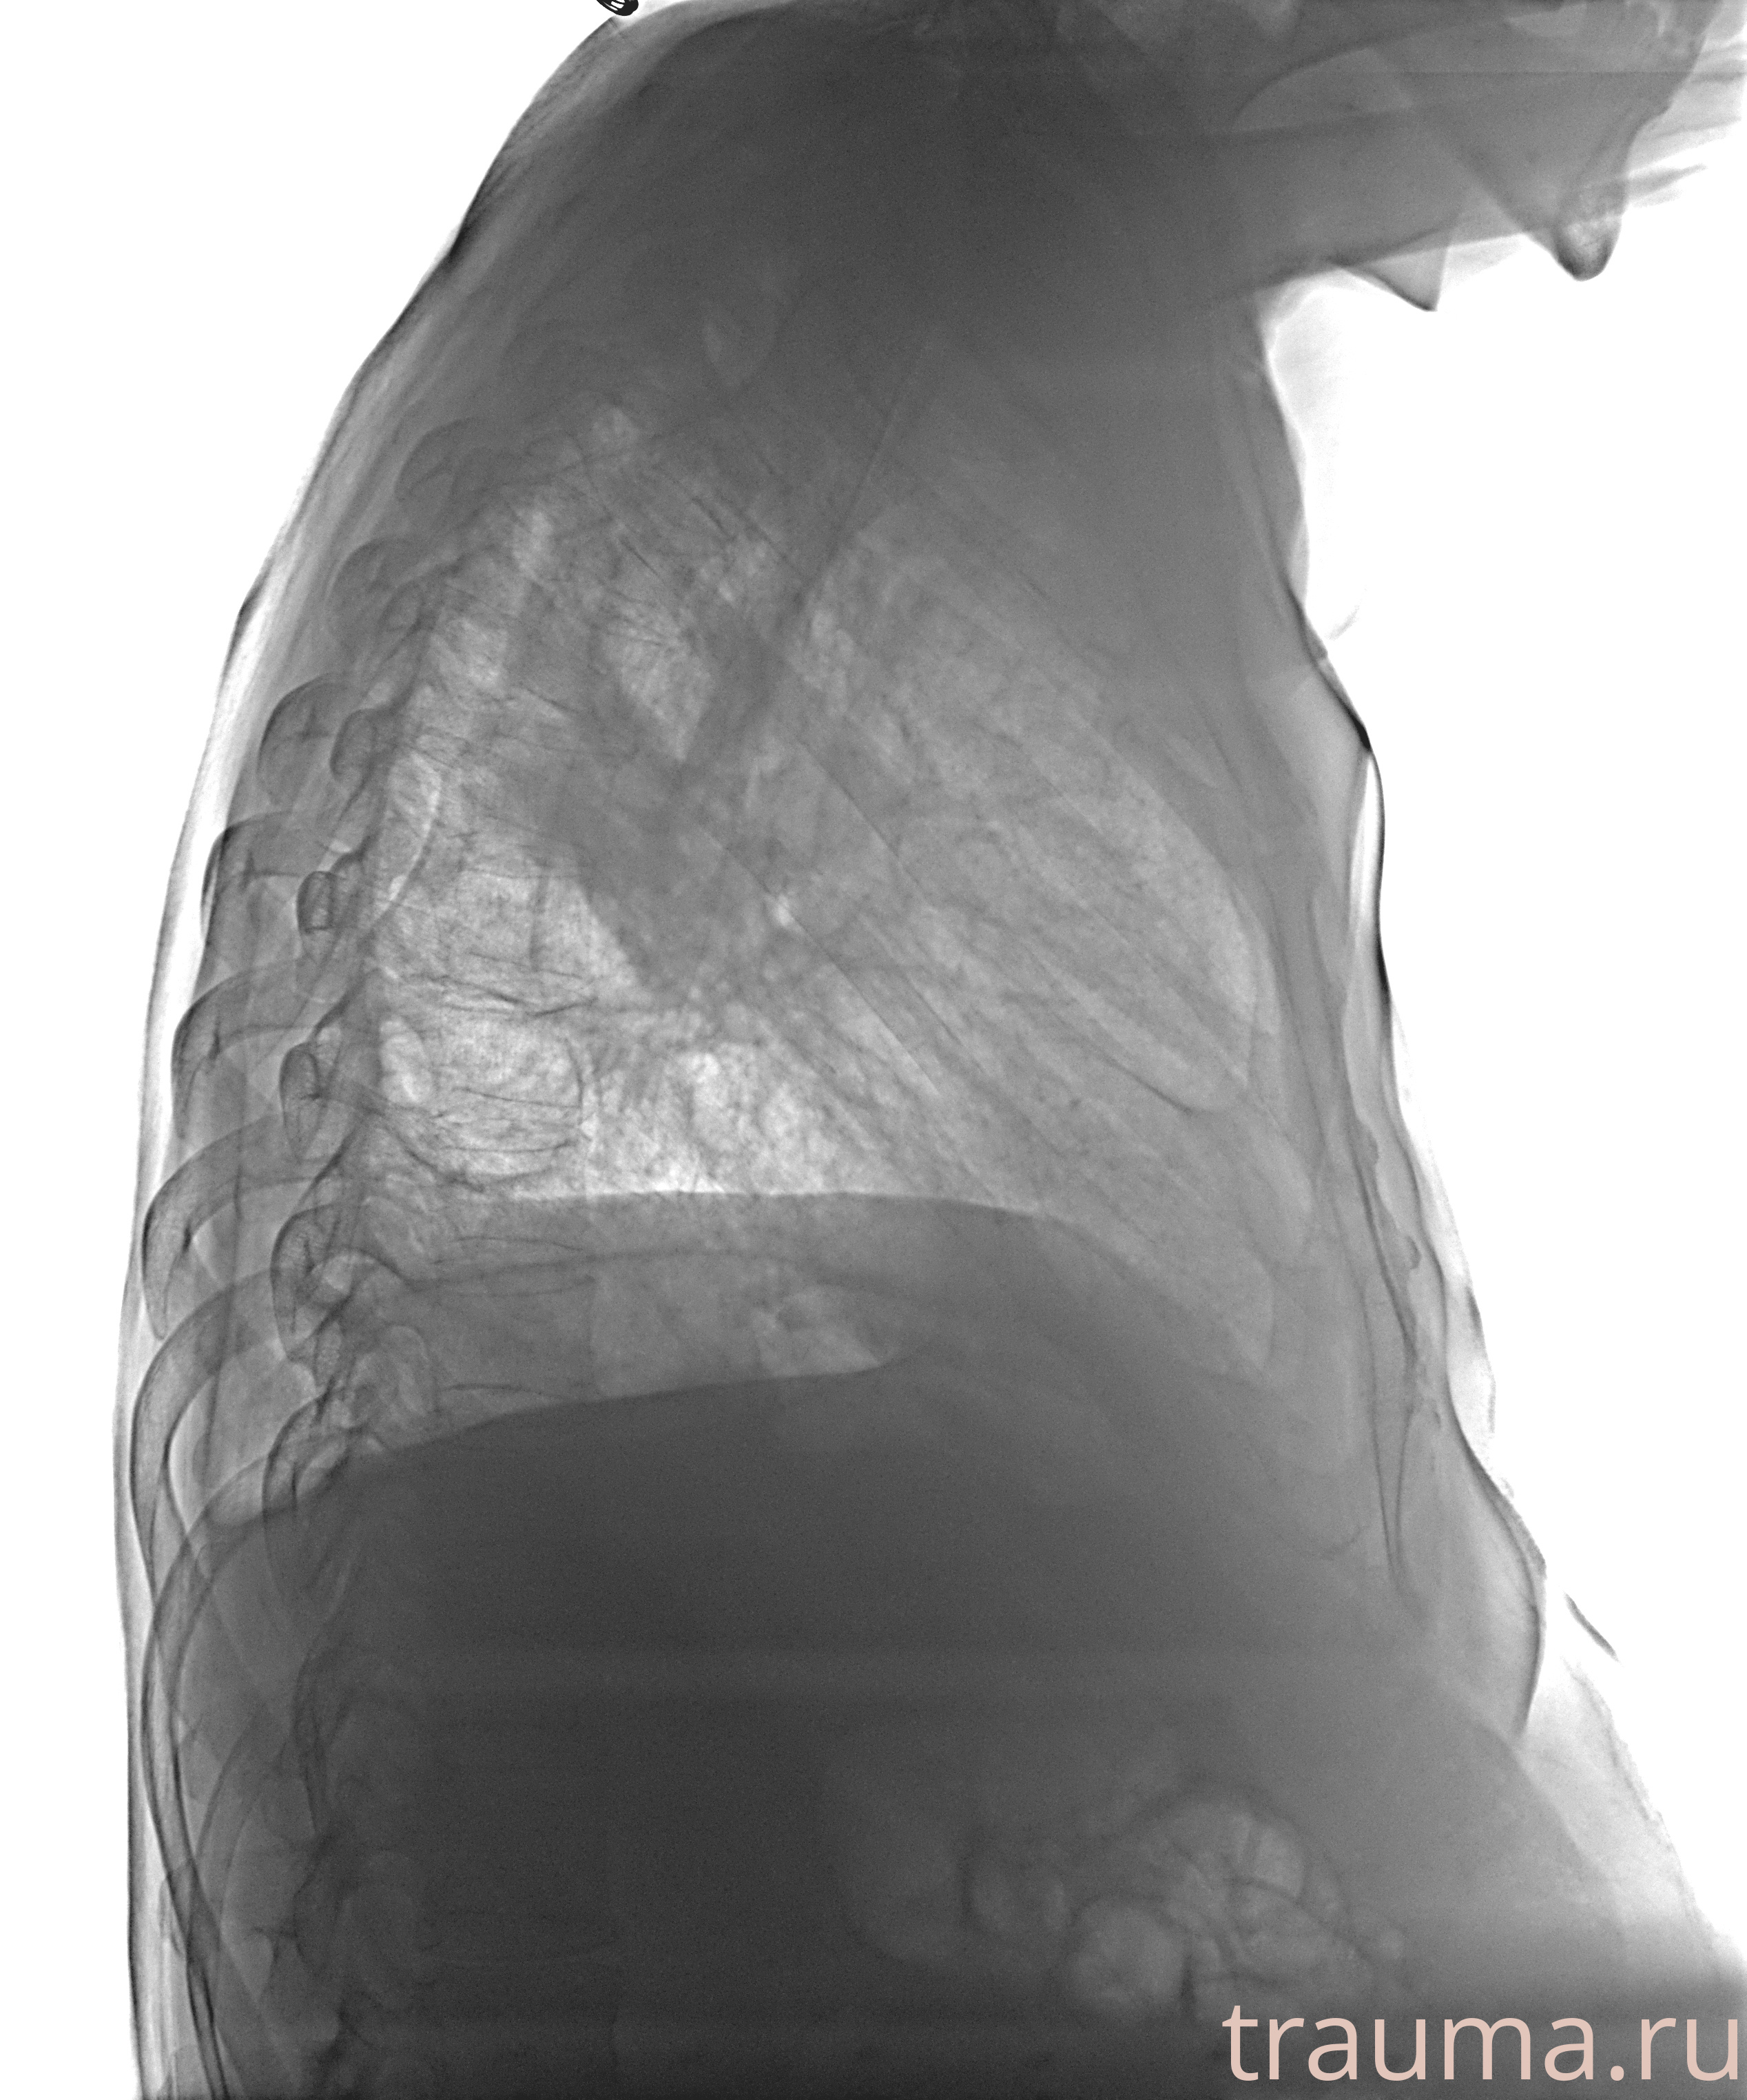

Рентгенограммы

Рентген на дому: по вашему адресу приезжает врач-рентгенолог, травматолог-ортопед с мобильным рентгеновским аппаратом, проводит диагностику травмы или заболевания, делает необходимые рентгенограммы, дает рекомендации по дальнейшему лечению. Получить качественные снимки в домашних условиях возможно благодаря уникальной методике, разработанной МосРентген Центром для института  Склифосовского

Образование в правом легком